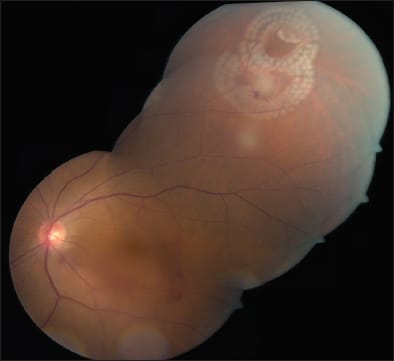

Figure 2. Pascal treatment of clustered peripheral tears using hemi arc patterns.

Figure 1. Panretinal photocoagulation of proliferative diabetic retinopathy with Pascal using a 200-micron spot size.